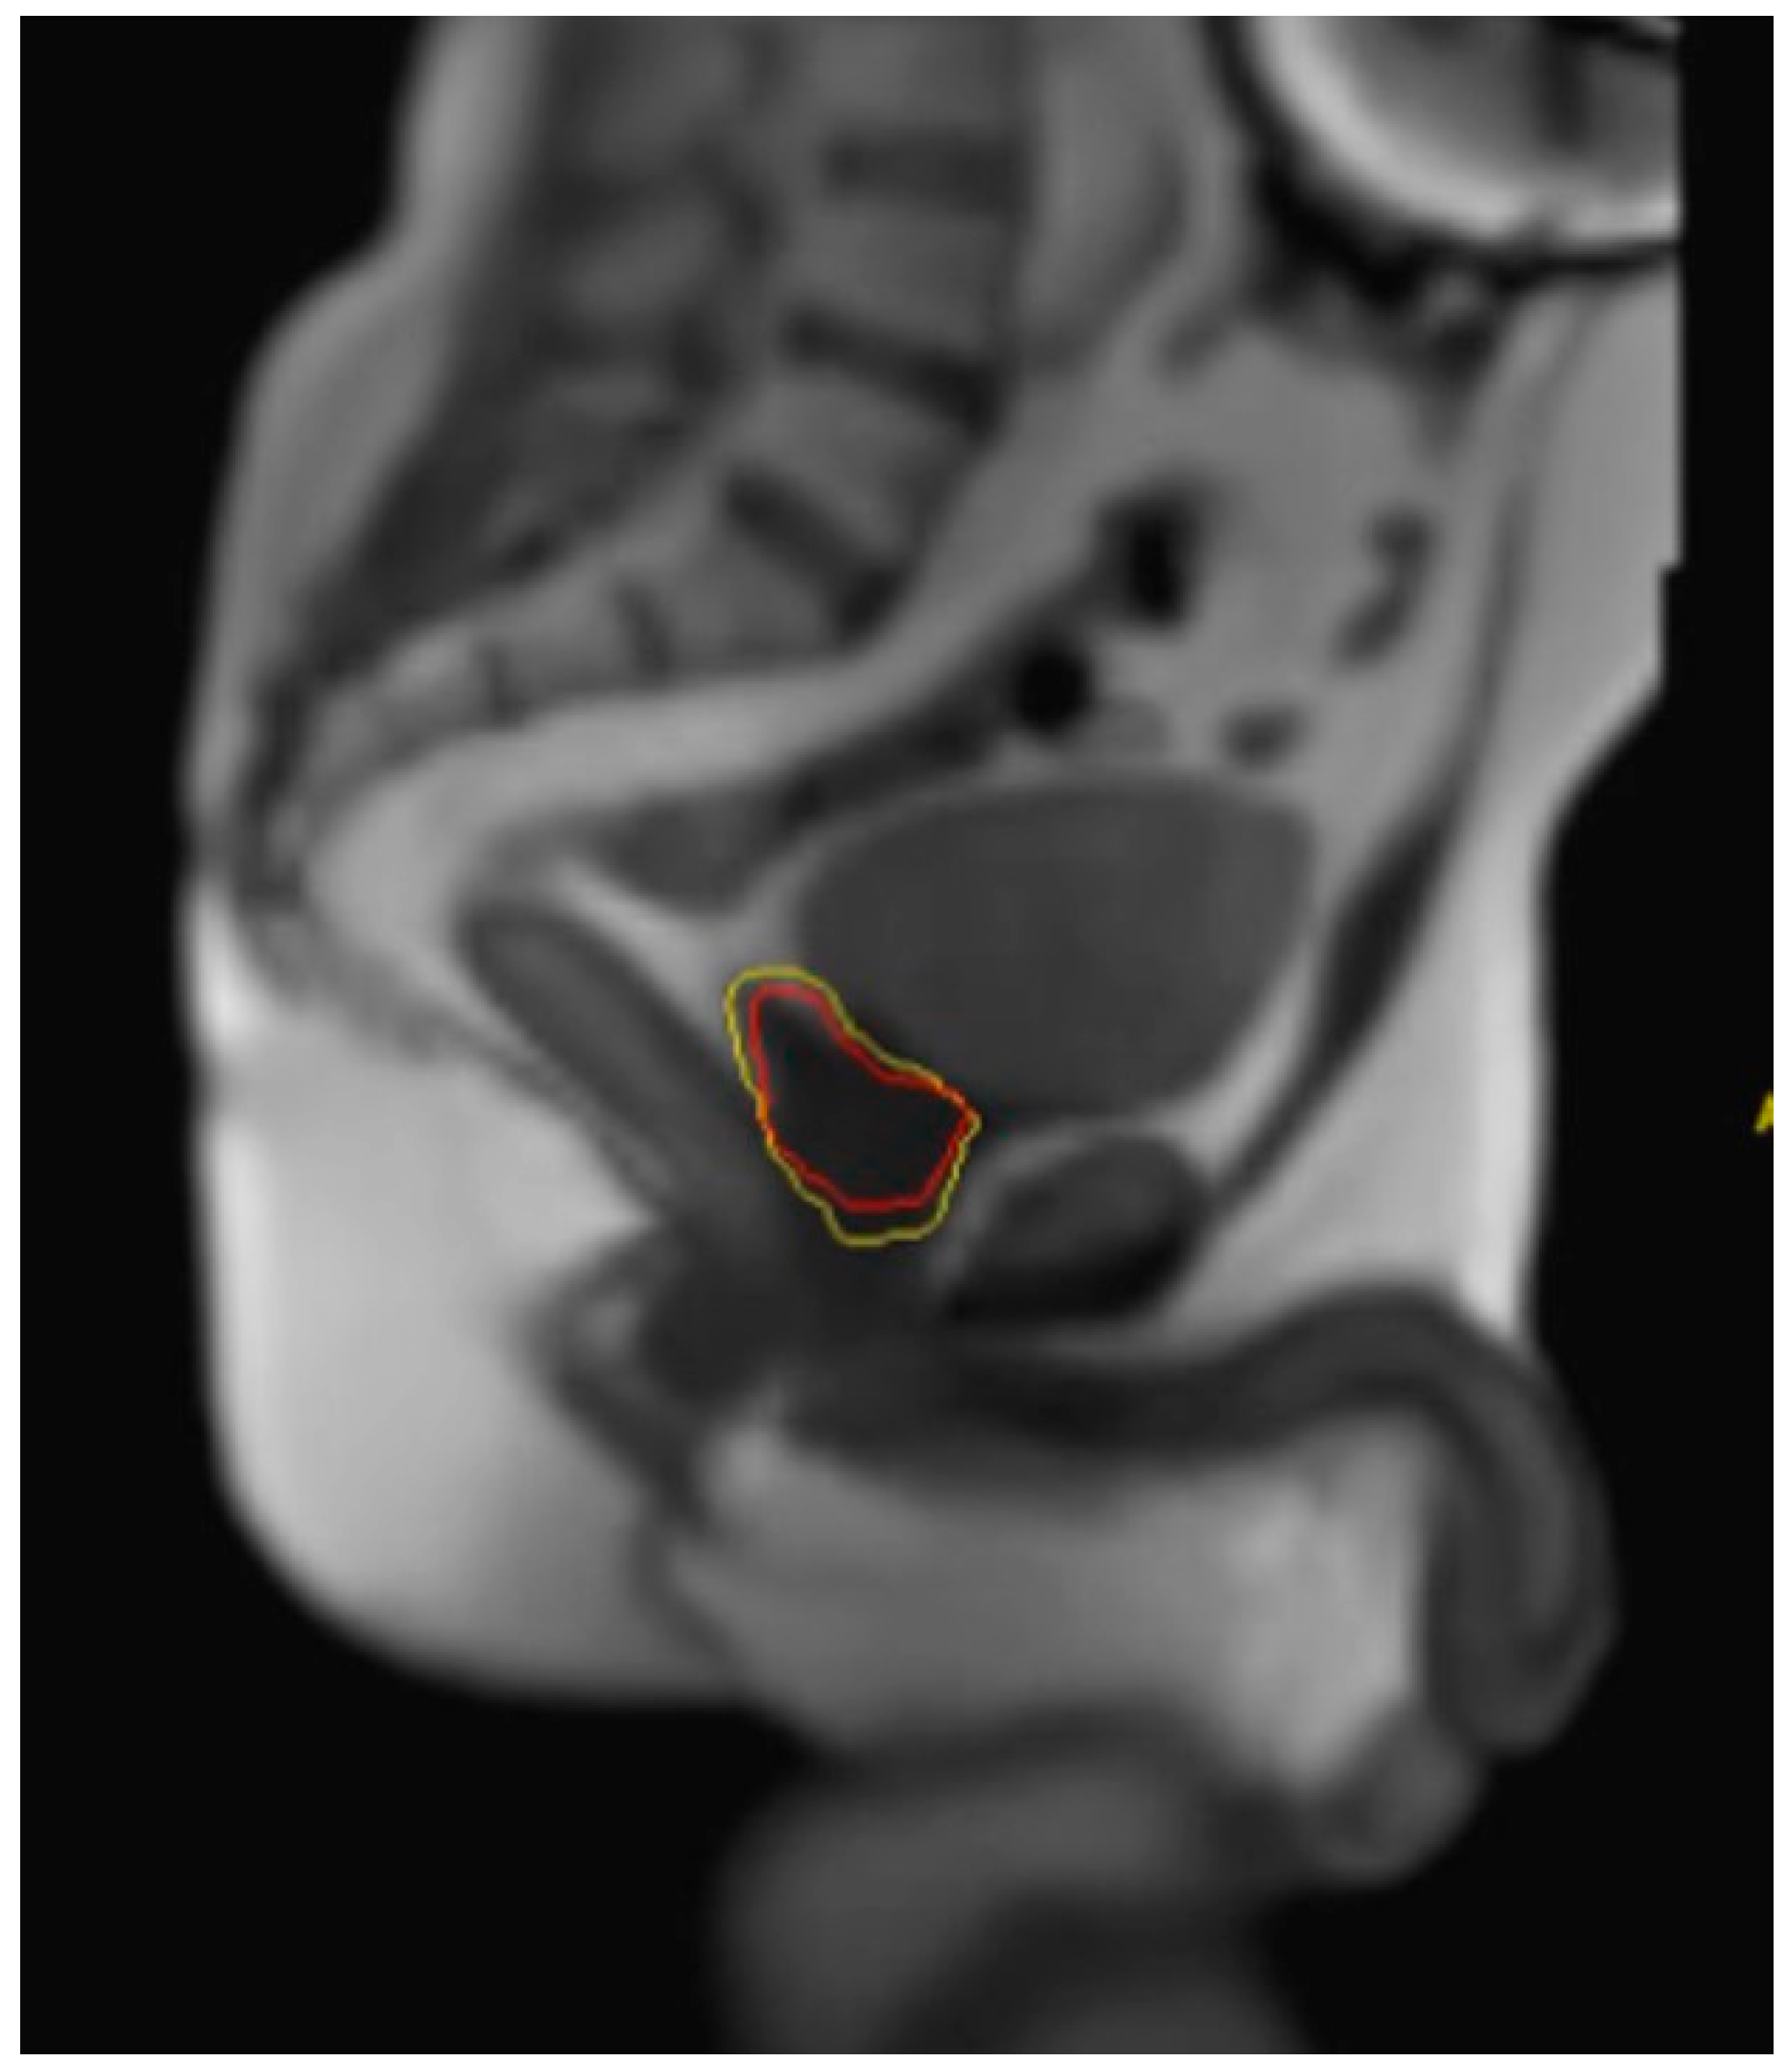

- Pham, J.; Savjani, R.R.; Gao, Y.; Cao, M.; Hu, P.; Sheng, K.; Low, D.A.; Steinberg, M.; Kishan, A.U.; Yang, Y. Evaluation of T2-Weighted MRI for Visualization and Sparing of Urethra with MR-Guided Radiation Therapy (MRgRT) On-Board MRI. Cancers 2021, 13, 3564. [Google Scholar] [CrossRef]

- Xu, D.; Ma, T.M.; Savjani, R.; Pham, J.; Cao, M.; Yang, Y.; Kishan, A.U.; Scalzo, F.; Sheng, K. Fully Automated Segmentation of Prostatic Urethra for MR-Guided Radiation Therapy. Med. Phys. 2023, 50, 354–364. [Google Scholar] [CrossRef]

- Pham, J.; Savjani, R.R.; Yoon, S.M.; Yang, T.; Gao, Y.; Cao, M.; Hu, P.; Sheng, K.; Low, D.A.; Steinberg, M.; et al. Urethral Interfractional Geometric and Dosimetric Variations of Prostate Cancer Patients: A Study Using an Onboard MRI. Front. Oncol. 2022, 12, 916254. [Google Scholar] [CrossRef]